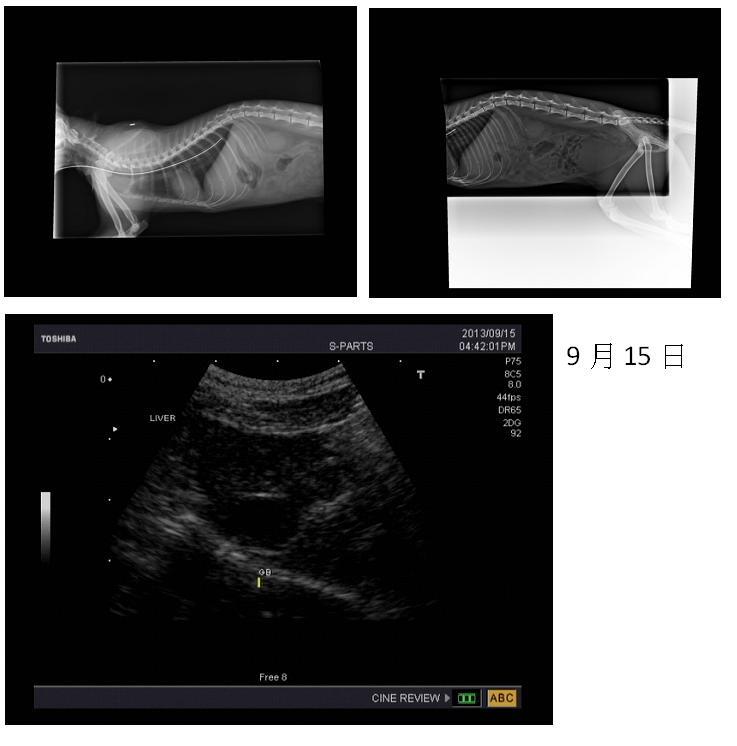

就拍了X光,

也做了血液檢查後,

也在做了血檢.X光.超音波...

2.X-ray 400*2